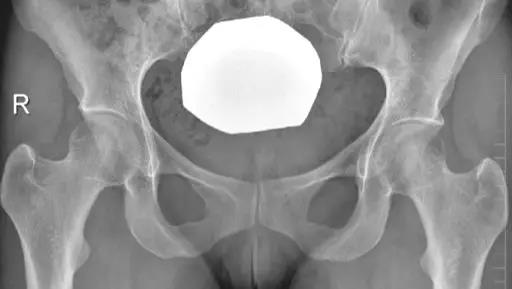

- 髋臼后倾

- 髋臼前缘线位于髋臼后缘线的外侧:阳性交叉征(8字征)。

- 髋臼后壁过度覆盖:髋臼后壁缘位于股骨头中心的外侧,即后壁征。

- 髋臼后突

- 髋臼唇骨化